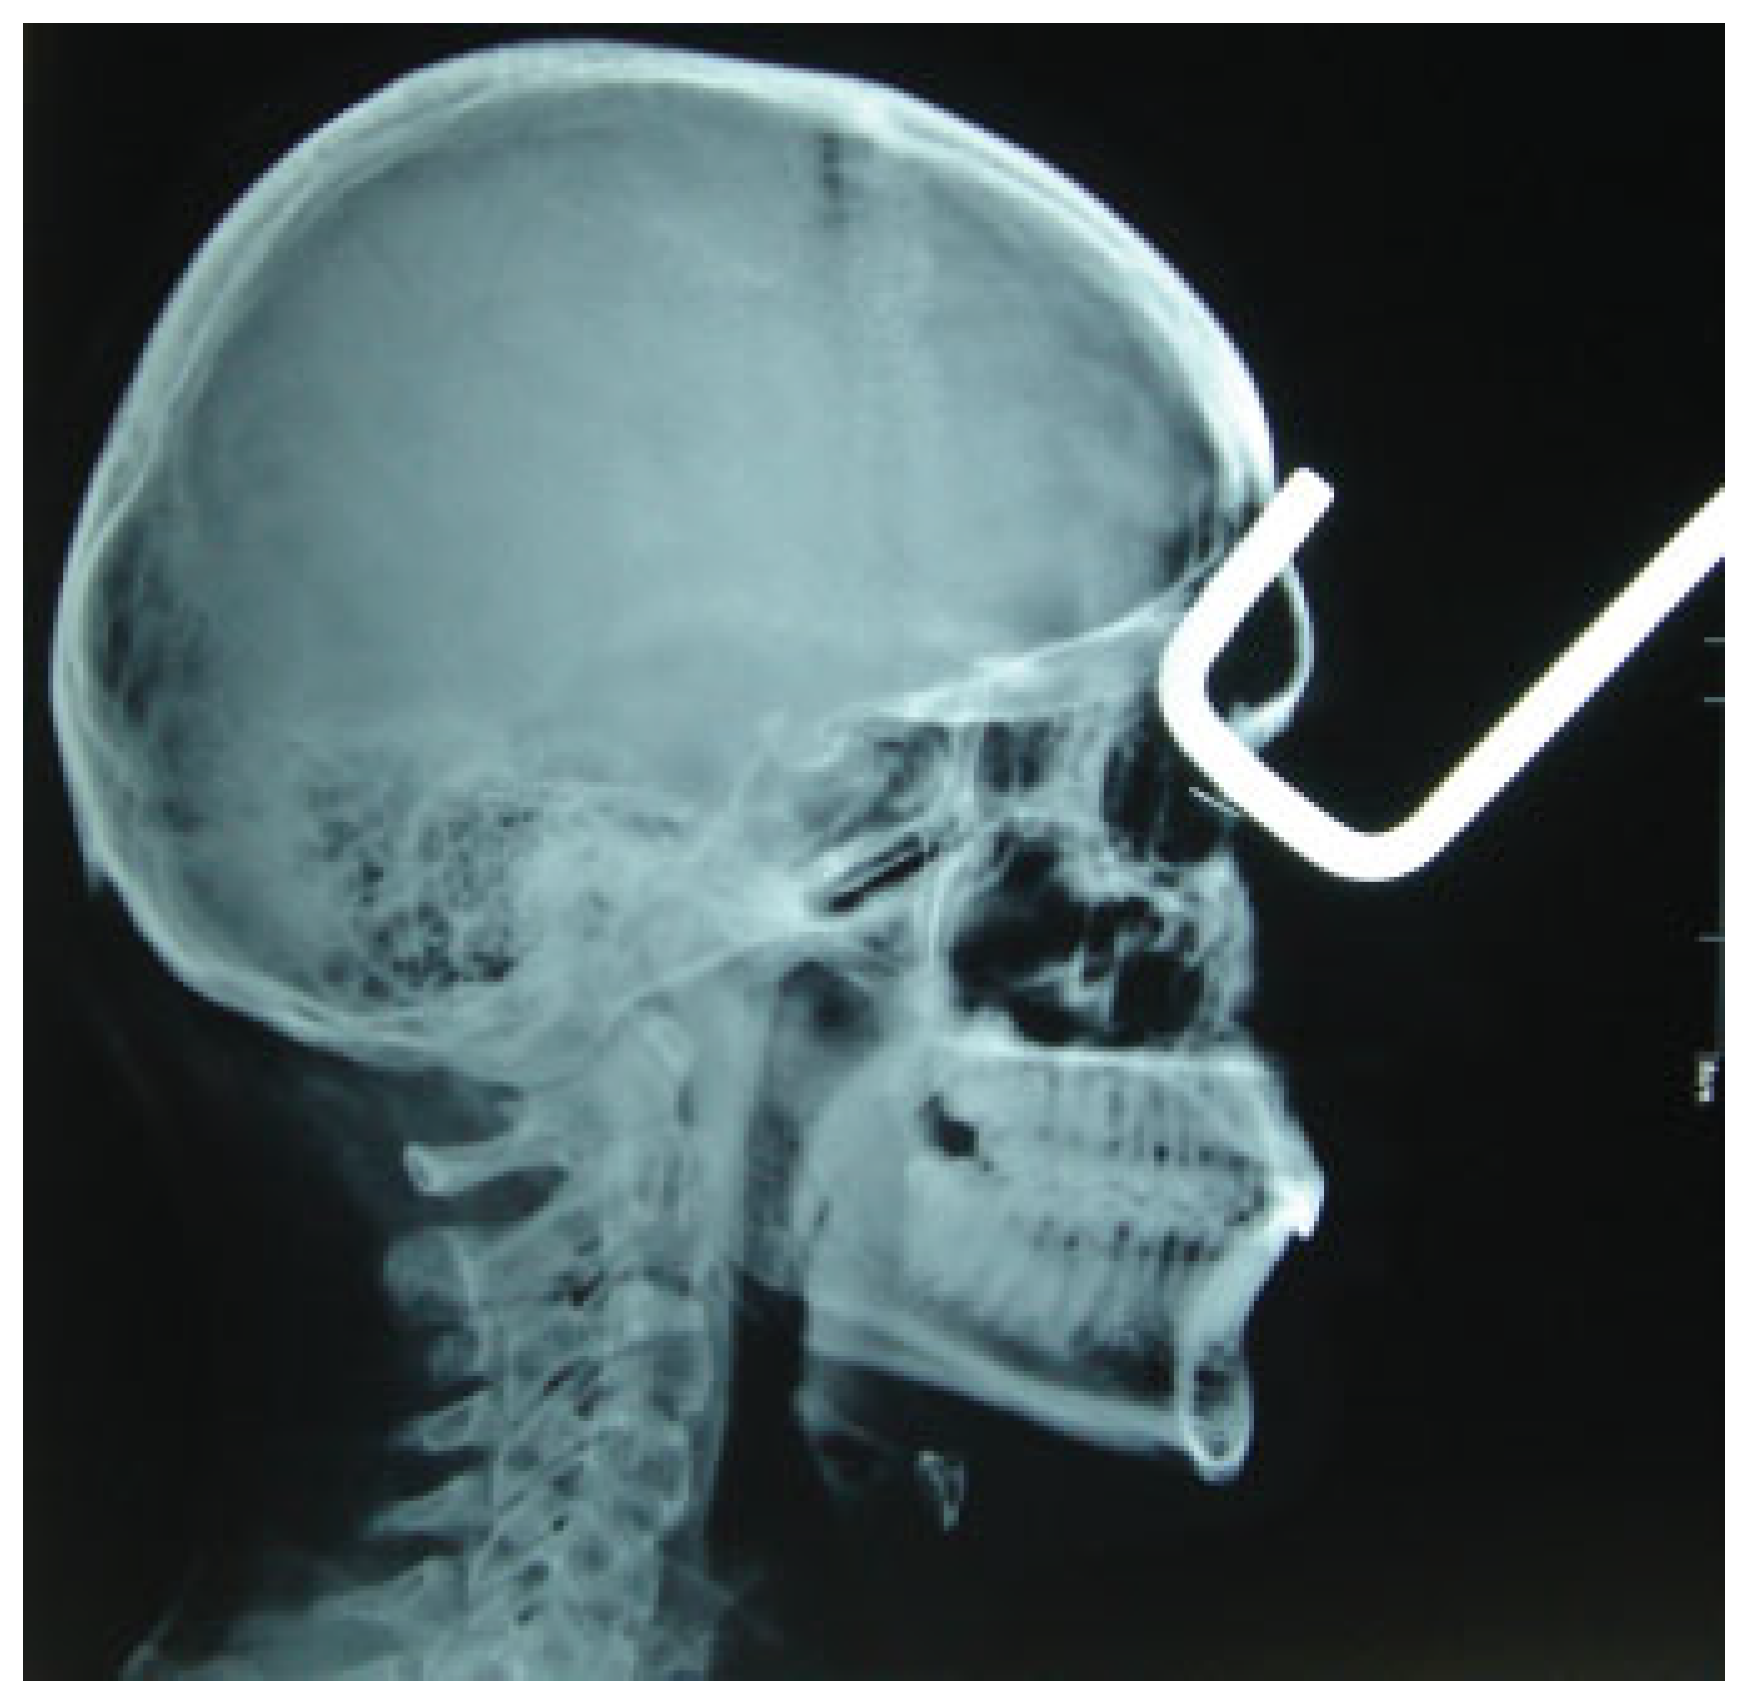

Transorbital Orbitocranial Penetrating Injury with an Iron Rod

:Case Report